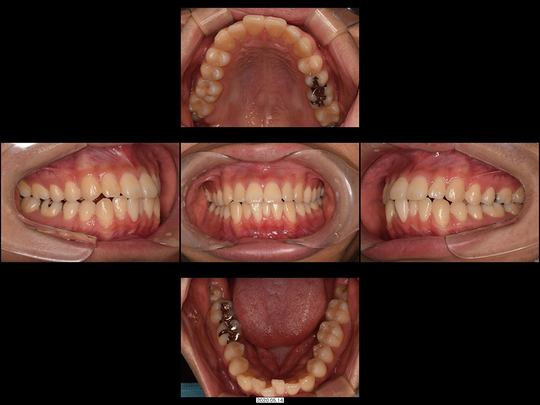

Tさん 20代 男性

矯正前

画像をクリックで拡大

矯正後

治療の説明

下前歯だけ、部分的なマウスピース型矯正装置を使った矯正治療をしました。非抜歯にて完了しています。

治療の期間・回数

9か月、12回

​費用

470,800円